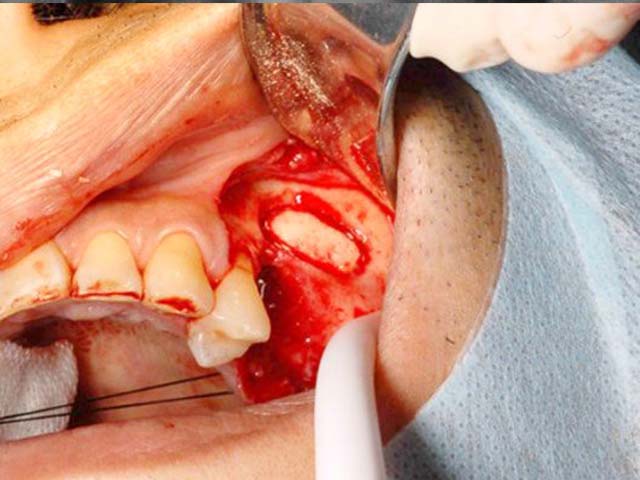

鼻竇增高術(側窗) 首頁 案例分享 人工植牙 鼻竇增高術(側窗) 鼻竇增高術(側窗) 製作多年的牙橋,牙根斷裂,發炎 鼻竇增高術 側面開窗 抬高鼻竇 鼻竇增高術 置入骨粉 覆蓋再生膜,保護骨粉 術後追蹤,傷口良好 裝戴正式假牙 完成 8年追蹤 左上牙根斷裂 植牙重建 九年追蹤